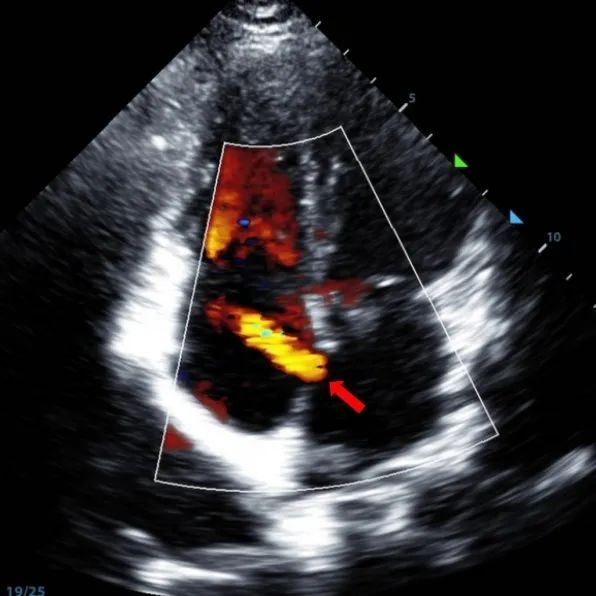

Ein 9-jähriger Mann mit secundum ASD (7,5-7,9mm) wurde mit einem MemoSorb-BDASD-I 12-mm-Okk luder und einem 12F-Fördersystem behandelt. Vor dem Eingriff wurden keine Komplikationen oder Komorbiditäten festgestellt.

Serial echocardiographic follow-ups showed stable device position and favorable cardiac remodeling. Gradual degradation confirmed the occluder's long-term safety and efficacy.